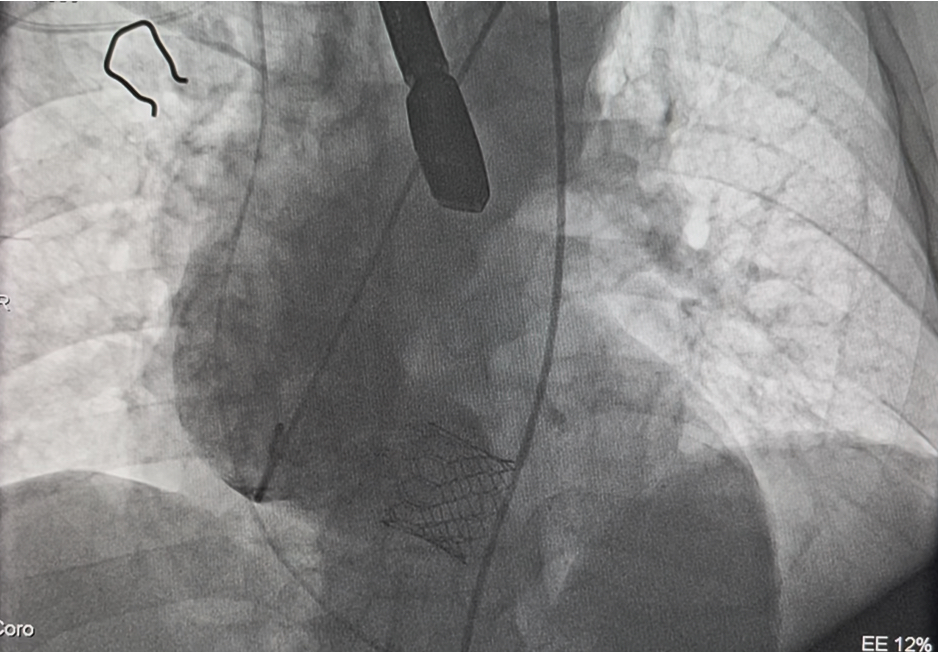

2025年10月27日,在南阳市中心医院东院区导管室里,正在进行着东院区的首例经导管主动脉瓣置换术(TAVR)手术。负责手术的是结构性心脏病病区杨侃教授,王登峰教授,范迪堃教授团队,接受手术的是一位73岁高龄主动脉瓣重度狭窄患者。监护仪屏幕上,绿色的波峰上下浮动,象征着心脏跳动的传出的滴滴声敲打在手术室每个人的心上。最后几秒,整个科室人员几乎屏住呼吸,眼睛紧紧盯着前方的瓣膜定位造影,空气仿佛凝固了一般,所有人都在等待着……瓣膜送达预定位置后,精准释放,立即开始工作。即刻造影及超声未见瓣周漏,主动脉瓣跨瓣压差正常,手术圆满结束!瞬间,手术室里的每个人都仿佛翻过了一座大山,如释重负!

10月27日,全员齐到位,在医院的大力支持及多学科的密切配合下,结构性心脏病病区杨侃教授,王登峰教授,范迪堃教授团队按照既定方案为老人实施手术,通过老人股动脉植入瓣膜,瓣膜输送、定位及释放......整个手术过程一气呵成。

手术后,即刻造影及超声提示未见反流,无瓣周漏,瓣膜植入位置良好,即刻超声提示主动脉瓣跨瓣基本无压差,未出现相关并发症,手术圆满成功。